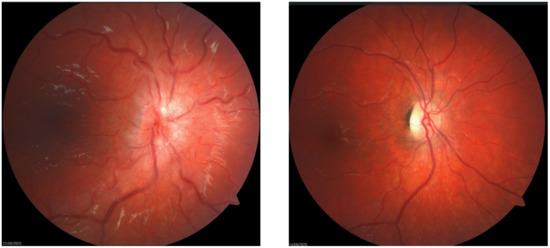

5.2. Signs

Examination and Investigations